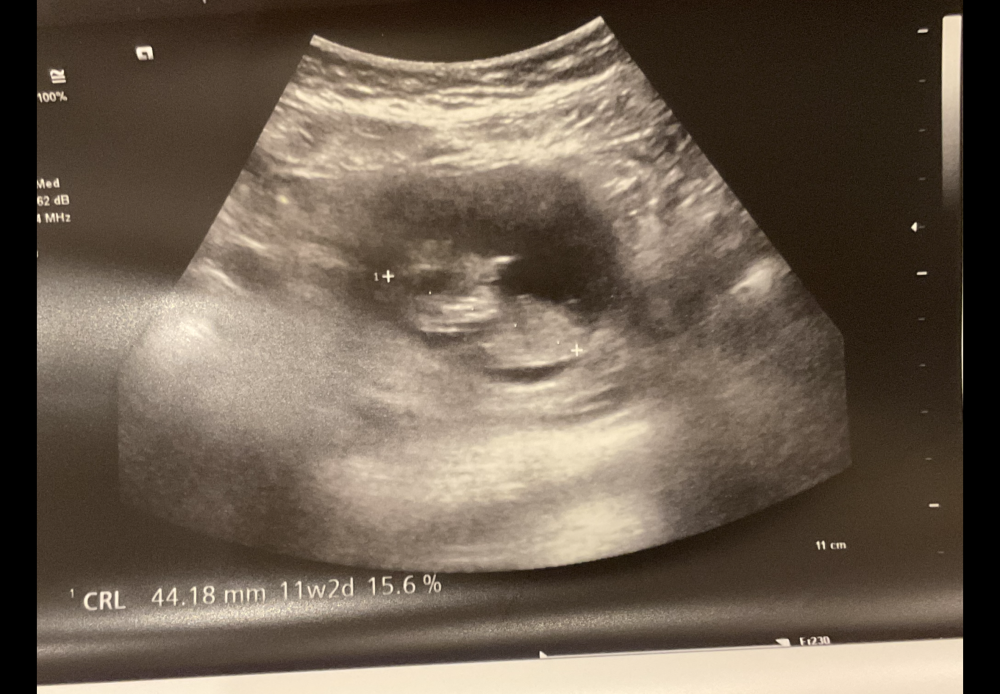

سونار اسبوع ١٢

الحين انزل صور ان شاء الله واضحة